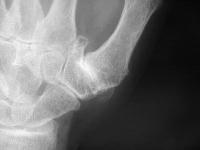

Before surgery, subluxation of the metacarpal base: